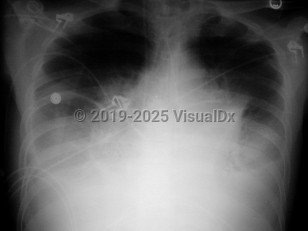

Inclusion criteria can be any one of the following: positive blood cultures, mediastinal adenopathy, or pleural effusions. The patient may also have nonspecific findings such as high fever, dyspnea, confusion, syncope, and nausea / vomiting. If diagnosed in this stage, the prognosis is still good if antibiotics are administered, pleural fluid is drained, and supportive care is provided.